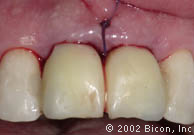

44. | 即刻种植术后的13个星期,病人第二次就诊时临时冠的唇侧观。 |